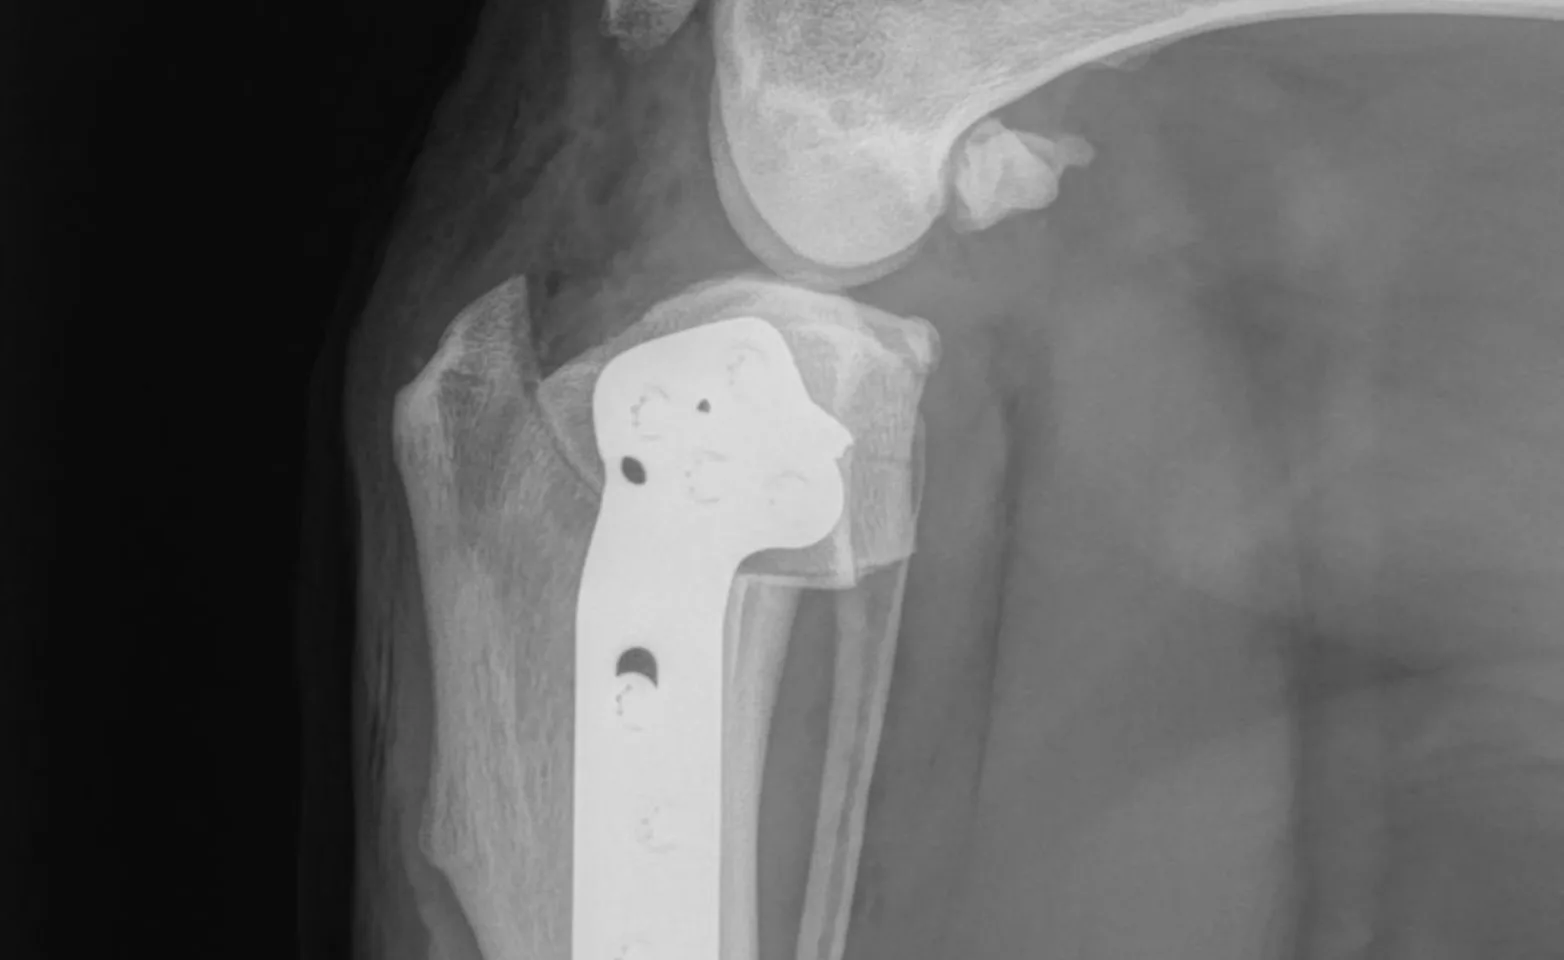

Tibial plateau leveling osteotomy (TPLO) for cranial cruciate ligament rupture

Total hip replacement (THR)